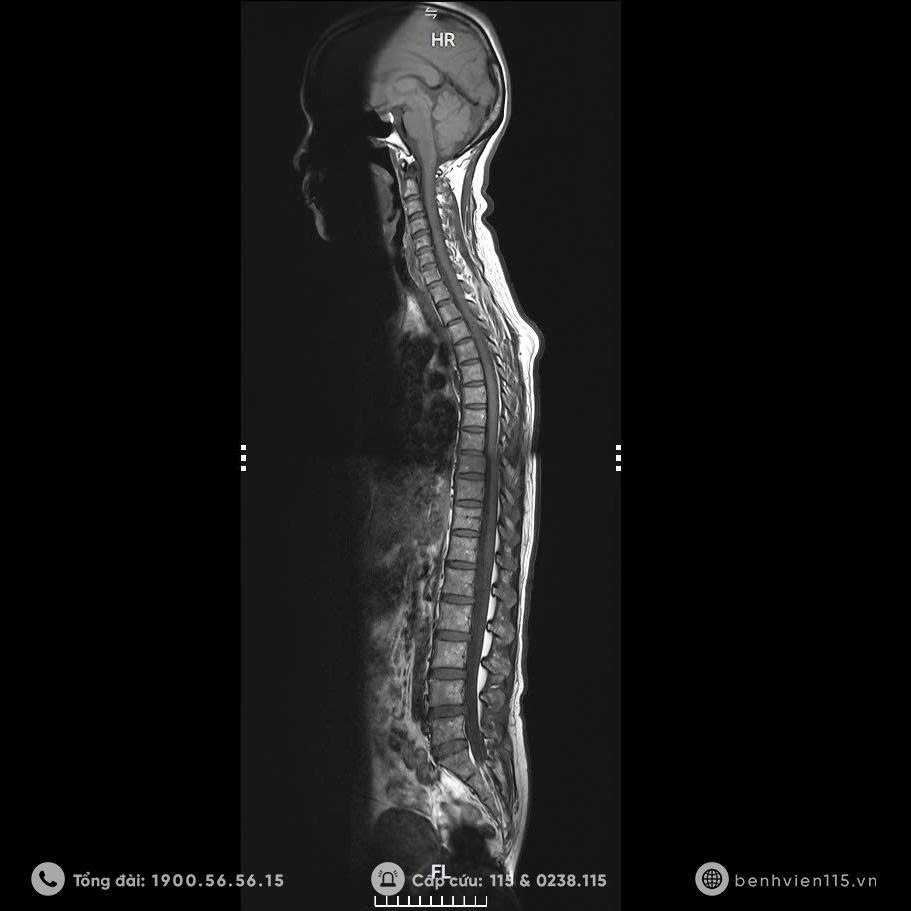

Hình ảnh cộng hường từ toàn thân trên máy MRI 3.0 Tesla

Một trong những phương pháp được sử dụng để tầm soát các bệnh lý tiềm ẩn chính là chụp Cộng hưởng từ (MRI) – Công cụ phát hiện sớm, nhanh chóng và chính xác. Ngày nay, MRI được coi là “tiêu chuẩn vàng” trong chẩn đoán hình ảnh các bệnh lý não, tủy sống và cột sống,…

MRI sử dụng từ trường và sóng radio để cung cấp hình ảnh chi tiết và chính xác về cơ thể. Chỉ mất khoảng 10 phút, hệ thống có thể ghi lại hình ảnh chi tiết bên trong cơ thể mà các phương pháp chụp X-quang hay CT scan thông thường khó phát hiện.

Nhờ đó, chúng tôi đáp ứng được nhu cầu phát hiện những bệnh lí chuyên sâu về đột quỵ, chấn thương,… Đặc biệt tầm soát khối u toàn cơ thể trong vấn đề phát hiện sớm bệnh ung thư, đánh giá những tổn thương di căn. Giúp phát hiện sớm nguyên nhân ẩn sâu như thoát vị đĩa đệm, thoái hóa cột sống, chèn ép rễ thần kinh, tai biến mạch máu não, khối u,…